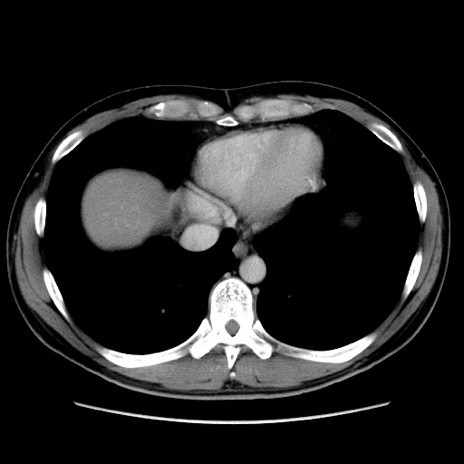

症例36(横断像)

【症例】20歳代 男性

【主訴】心窩部痛

【現病歴】今朝より上腹部痛あり。一旦軽快していたが再度出現したため救急要請。昨日夕に白身の魚を含む刺身を食べた。

【身体所見】BP 136/89mmHg、HR 74/min、BT 37.0℃、腹部:膨満、軟、心窩部に圧痛あり。反跳痛なし、筋性防御なし、腸雑音やや亢進あり。

【データ】WBC 17700、CRP 0.48